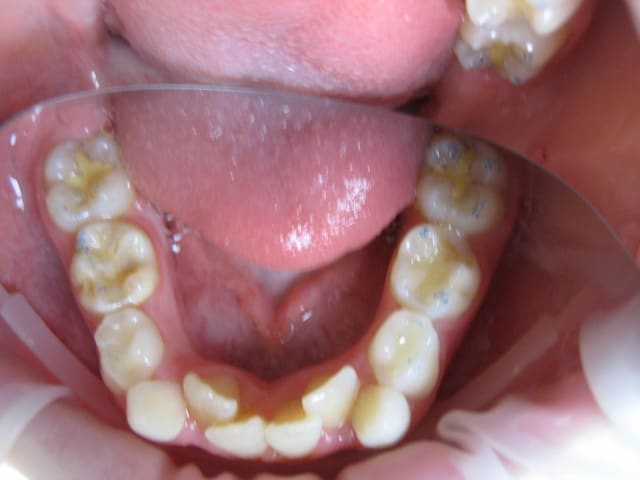

Je suis entrain de faire une observation clinique d'une patiente de 10 ans.

Elle présente une linguo-version et une égression des incisives maxillaires et mandibulaires. Le truc c'est que les racines de 11 et 21 semblent bien positonnées sur la télé de profil, alors que les faces vestibulaires sont très lingualées.

Photos endobuccales  2  wxrxfq - Eugenol

je crois que la forme très bombée de la couronne de centrale sur la radio, et qu'on ne voit pas sur les photos, est due à la superposition des quartes inciives. Quand au traitement, il s'agit d'un traitement classique d'un cas de classeII div 2.

Attention quand même aux racines des centralesavant de commencer, une retroalvéolaire pourrait être utile.